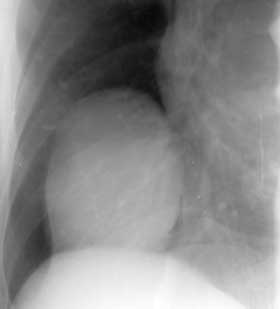

Диагностика образований, расположенных в проекции кардио-диафрагмальных углов.

Рис. 2. Целомическая киста перикарда.